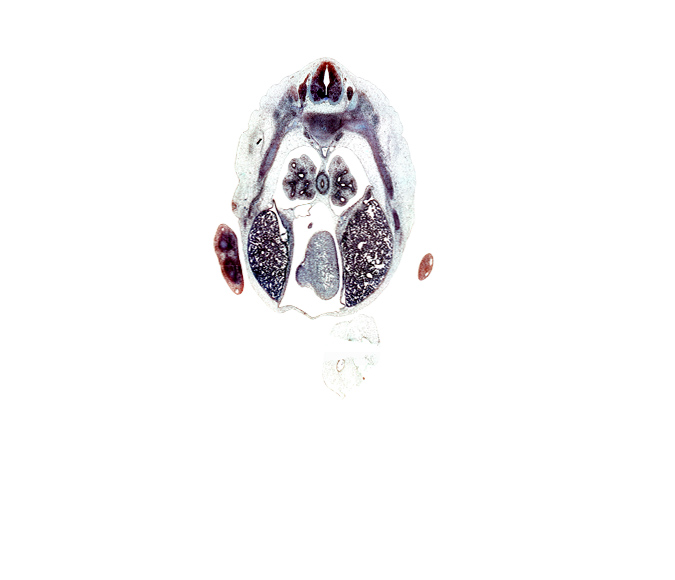

Carnegie Embryo #9325 | Location: 19-4-3

Keywords: T-6 / T-7 intervertebral disc, T-6 spinal ganglion, anterior interventricular sulcus, aorta, azygos vein, caudal edge of coronary sinus, caudal edge of right ventricle, central canal, central tendon of diaphragm, esophagus muscularis, heart prominence, inferior vena cava, intermediate zone, lateral basal tertiary bronchus, left lobe of liver, left ventricle, loose mesenchyme, marginal vein, marginal zone, mesonephros, pericardial cavity, posterior basal tertiary bronchus, right lobe of liver, sympathetic trunk, ventricular zone

Source: The Virtual Human Embryo.